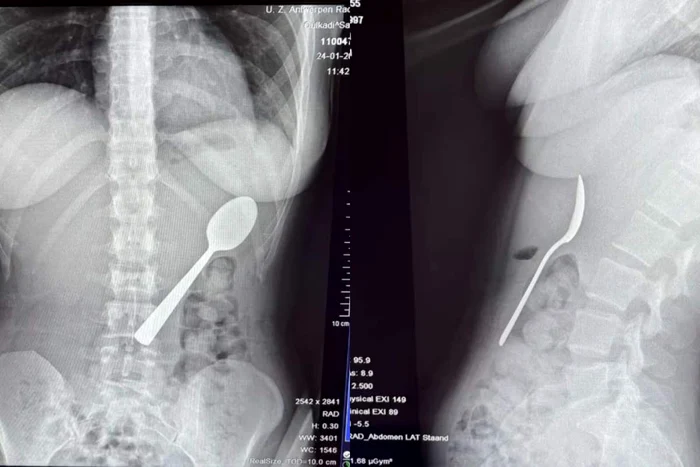

O tânără a înghițit o lingură de 17 cm din cauza câinelui: „Fie înghițeam, fie mă sufocam”

0O femeie de 28 de ani din Belgia a trăit momente terifiante după ce a înghițit accidental o lingură de 17 centimetri. Incidentul s-a produs în timp ce mânca iaurt pe canapea, iar totul a pornit de la o reacție neașteptată a câinelui ei, un energic Hungarian Vizsla pe nume Marley.

Medicii au decis să îi îndepărteze lingura sub anestezie locală, evitând o operație deschisă. Procedura a fost delicată, necesitând rotirea lingurii în interiorul stomacului pentru a putea fi extrasă în siguranță.